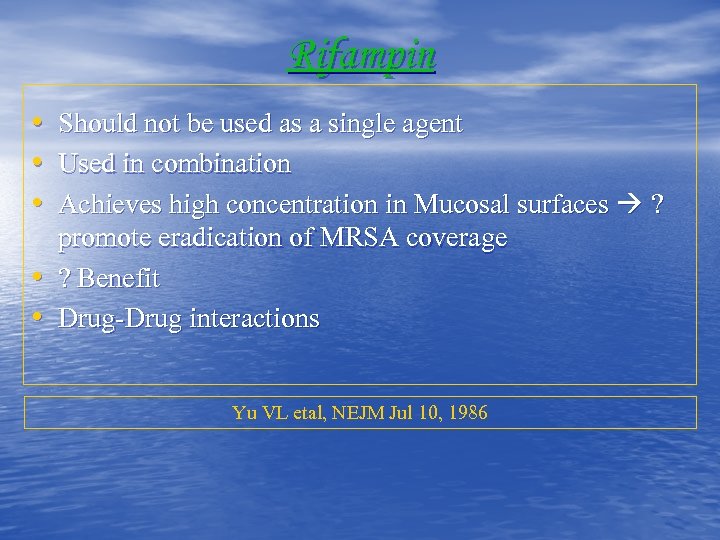

Rifampin • Should not be used as a single agent • Used in combination • Achieves high concentration in Mucosal surfaces ? • • promote eradication of MRSA coverage ? Benefit Drug-Drug interactions Yu VL etal, NEJM Jul 10, 1986

Rifampin • Should not be used as a single agent • Used in combination • Achieves high concentration in Mucosal surfaces ? • • promote eradication of MRSA coverage ? Benefit Drug-Drug interactions Yu VL etal, NEJM Jul 10, 1986